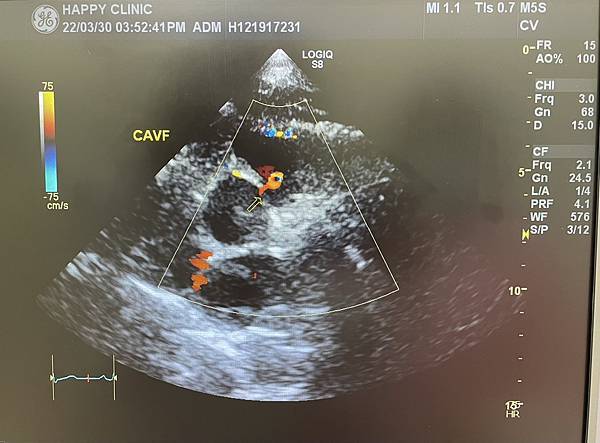

案例分享 - 冠狀動靜脈廔管

賴先生,59歲,具有三高病史,包含高血壓、高血脂和高血醣。近期出現偶發性胸悶、胸痛現象,至醫院進行心電圖、運動心電圖與心臟超音波檢查,卻無發現任何異常。